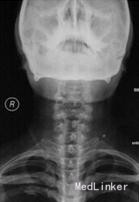

外院颈椎X线片检查显示颈椎退行性改变、颈椎不稳,双侧臂丛B超检查显示左侧锁骨下动脉在锁骨上凹处将神经股部完全隔离成两部分,右侧神经股部的分布也与正常有异,肌电图检查提示双上肢慢性神经源性损伤电生理表现,主要累及C8-T1神经,不排除臂丛下干损伤可能,遂诊断为双侧胸廓出口综合征,建议手术治疗,但患者未接受手术治疗。 2个半月后患者来我院就诊,颈椎CT检查显示C3-4、C5-6、C6-7椎间盘突出、颈椎退行性变,诊断为“双侧胸廓出口综合征、颈椎退行性变”,建议手术治疗。 3个半月后患者入院,查体示C5-6、C6-7棘突及左侧棘旁压痛,双侧胸锁乳突肌及颈外静脉交叉点压痛(以左侧为重),左肩胛内上角压痛,左前臂内侧感觉及左手感觉减退,痛温觉减退;双肩外展肌肌力Ⅴ级,双侧肱二头肌、肱三头肌肌力Ⅴ级,双手握力减退(以左手为重)。